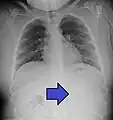

| An endoscopy image of the stomach, showing a foreign body in the form of a toothbrush. | |

One of the most common locations for a foreign body is the alimentary tract.

It is possible for foreign bodies to enter the tract from the mouth or rectum.